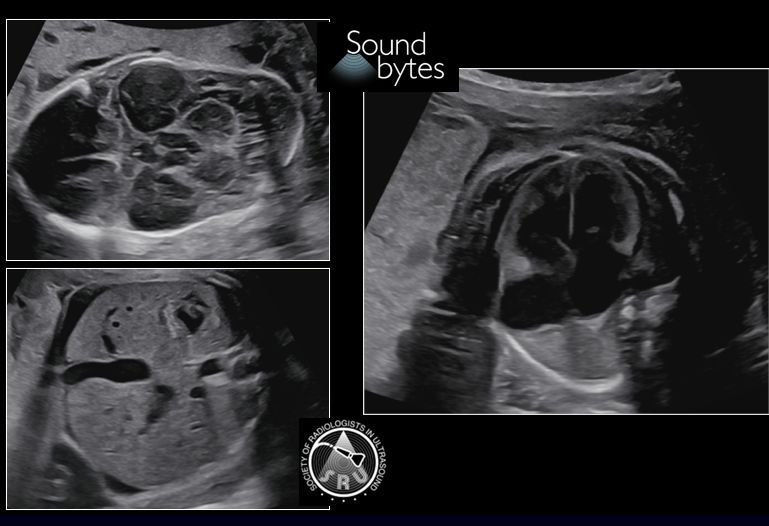

@sruradiology

SRU Radiology

8 days

Pregnant woman w history of seizures presents for 2ndT anatomy scan. What's your sound diagnosis? Case courtesy of Dr. April Griffith, U of UT #RadResidents #ultrasound #RadInTraining